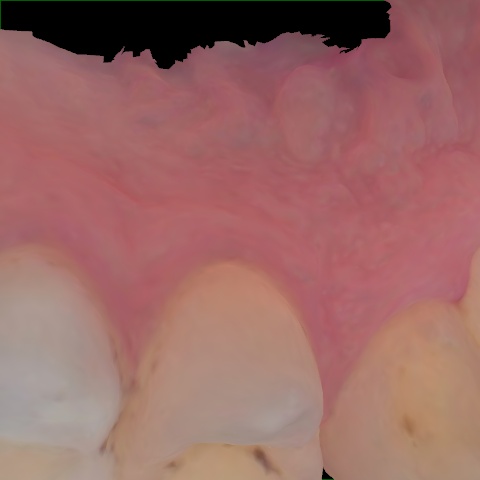

NHD39969

Annotated as "Good"